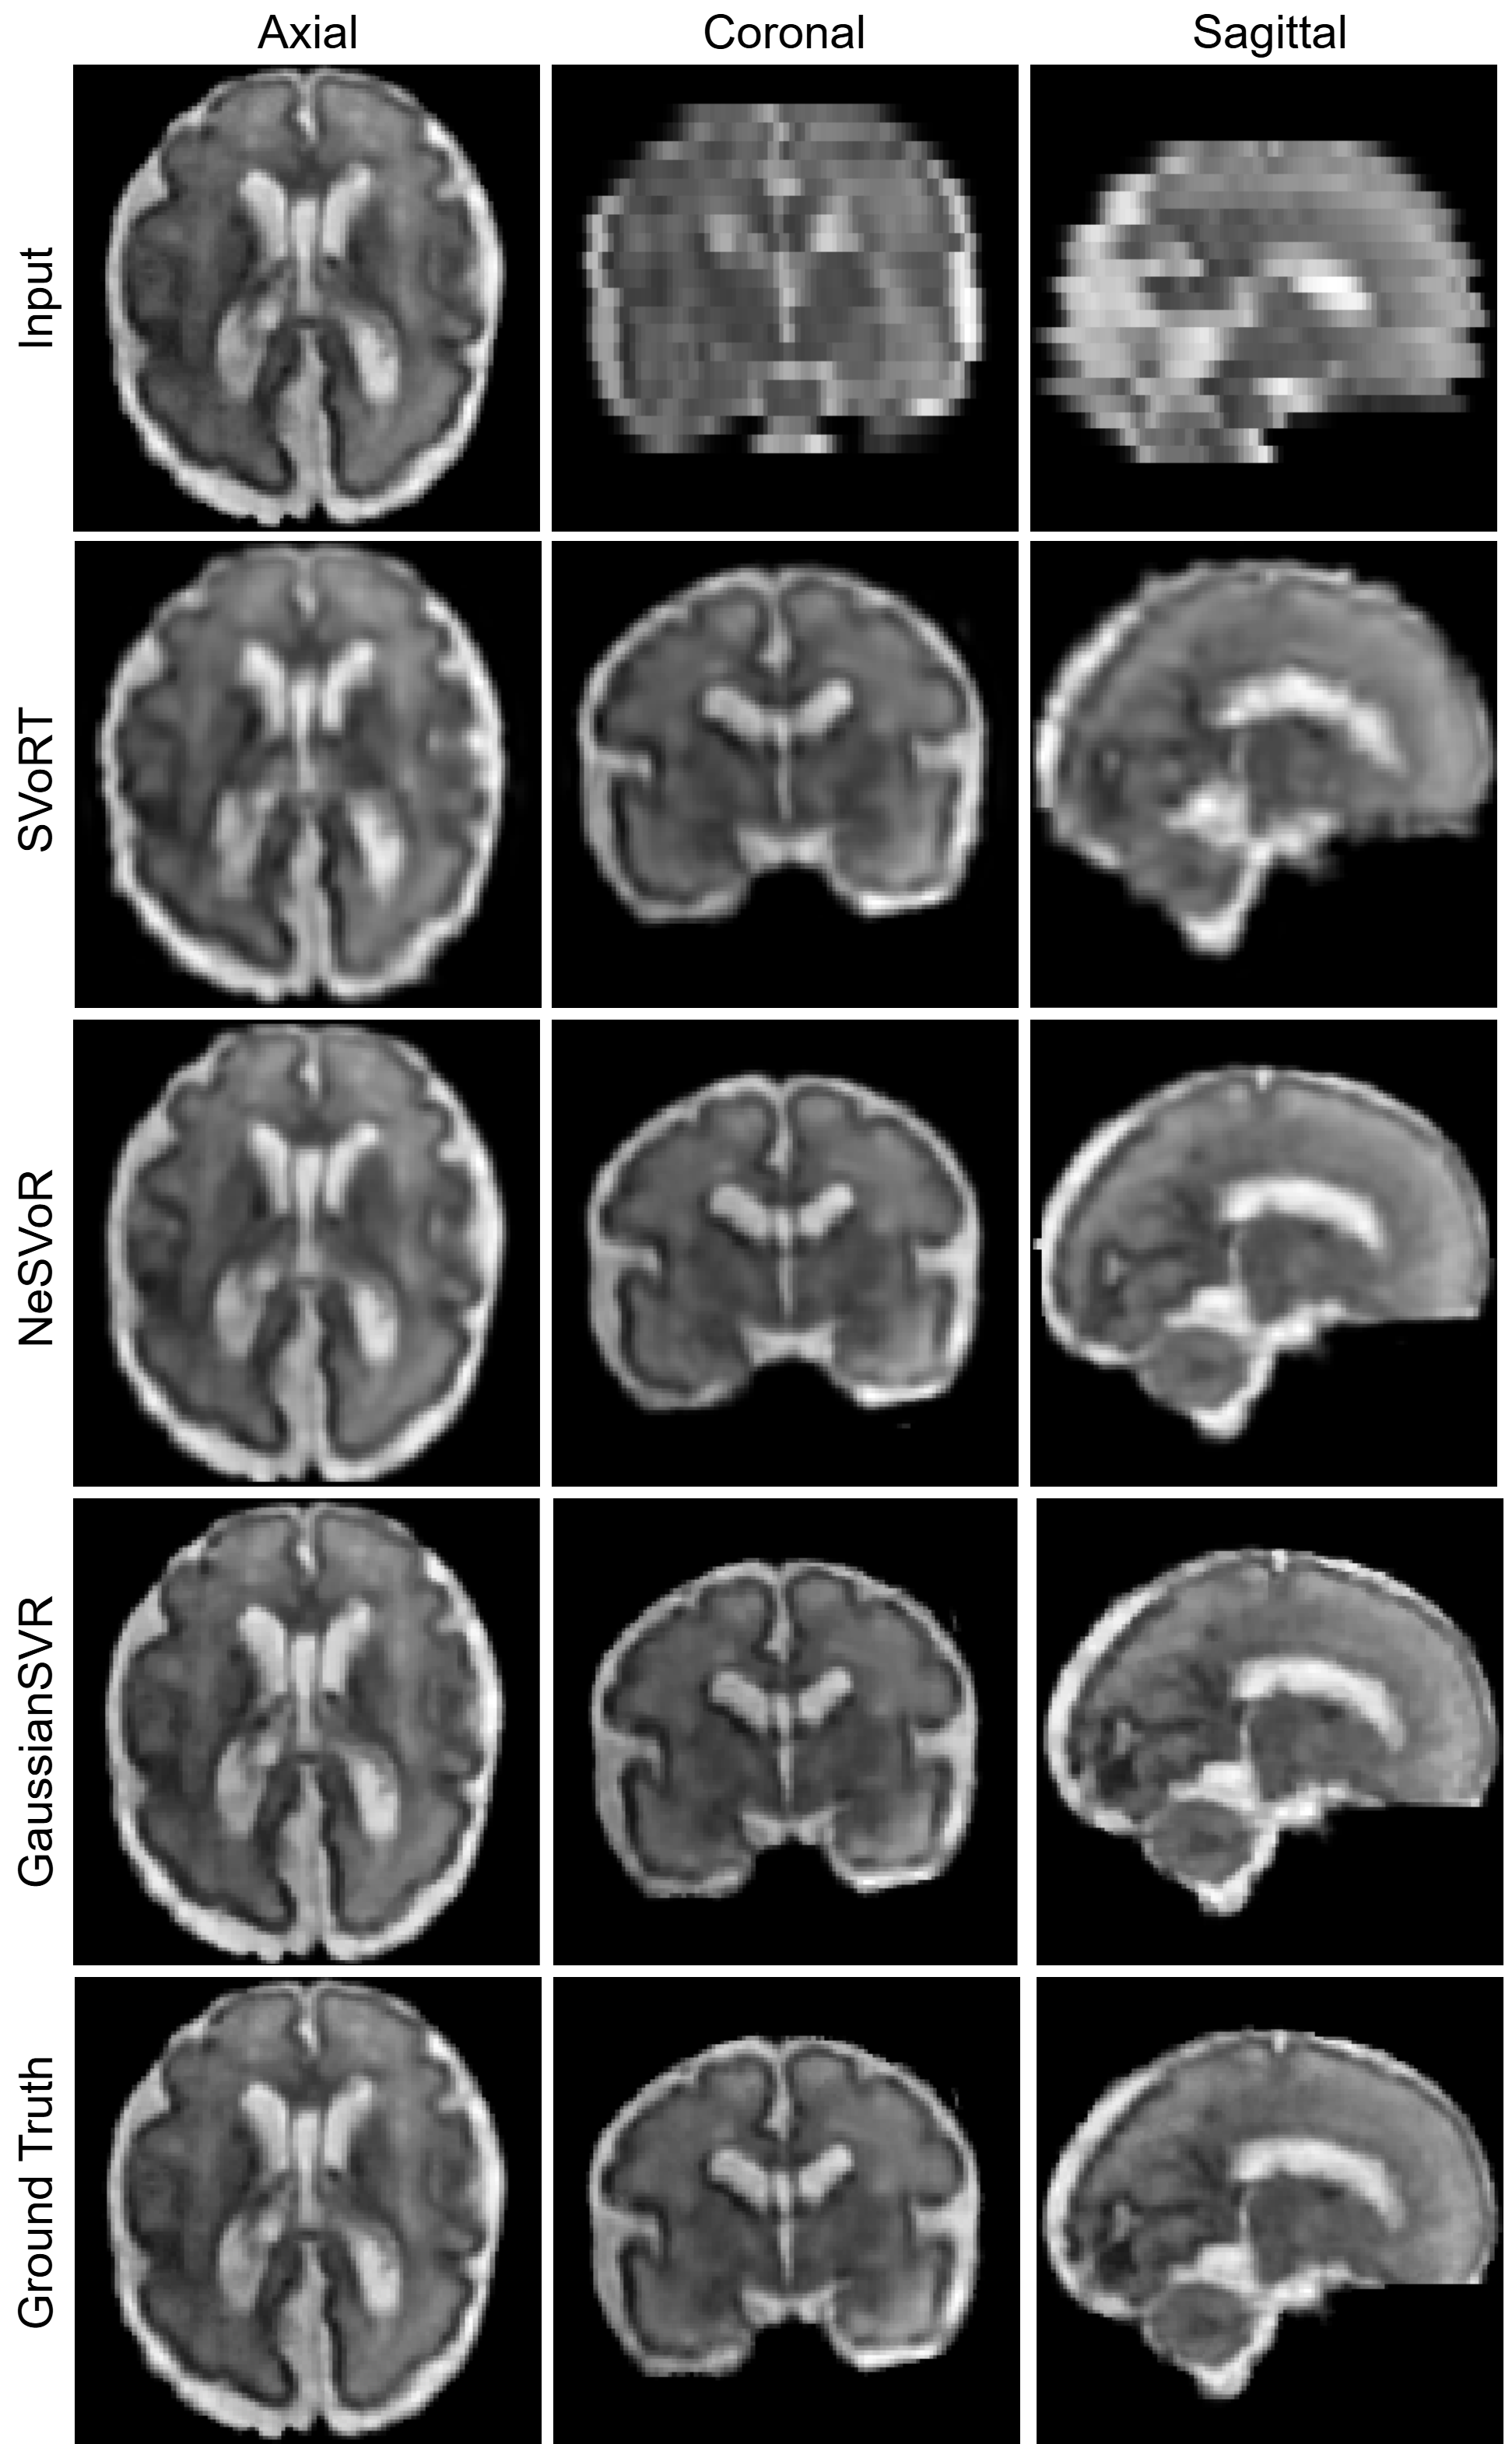

Refer to caption

Fig. 2: Qualitative volumetric reconstruction results on a single subject from motion-corrupted scans on the FeTA dataset.

Comparison studies. Table 1 reports the quantitative volumetric reconstruction performance of 3D fetal brain MRI on the FeTA dataset. We report the mean and standard deviation of the reconstruction results of the 30 test subjects. It can be observed that GaussianSVR achieves the highest reconstruction accuracy, achieving a 2.9% improvement in terms of PNSR compared to the second-best approach, NeSVoR. These results demonstrate that GaussianSVR substantially outperforms existing reconstruction approaches in both structural preservation and intensity consistency. The notably higher SSIM and lower NRMSE indicate that GaussianSVR more effectively maintains anatomical integrity and minimizes reconstruction artifacts. Figure 2 shows the qualitative reconstruction results of GaussianSVR compared with other baseline methods. It can be observed that GaussianSVR can reconstruct more fine-grained details. Compared to NeSVoR, GaussianSVR can reconstruct the volume with sharper details, demonstrating that Gaussian representations can achieve high-fidelity volumetric reconstruction.